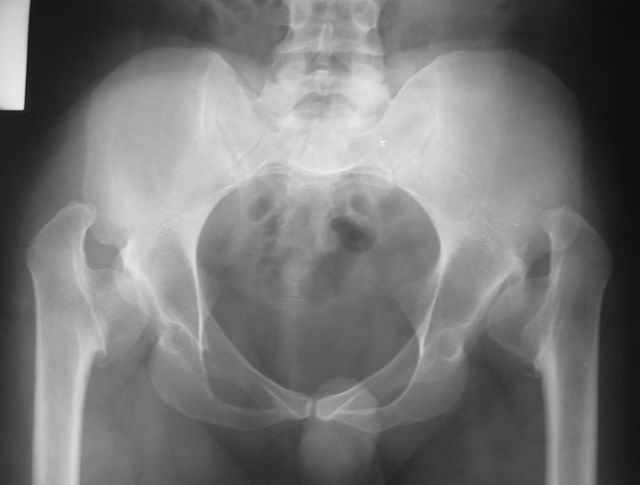

Dear All,This 27 year old presented to a colleague, about 2 years back, with complaints of bilateral hip pain. He was treated symptomatically, but now has increasing pain, and walking distance is being limited.

On examination, he has got a lordotic gait, Trendelenberg negative, bilaterally, hip movements fairly good, with no FFD.X-rays are attached.Kindly give your opinions regarding management and future prognosis.Thanks and regardsMuhammad Amin Chinoy FRCS

It appears that this patient has bilateral congenital hip displasia, as presented on the radiographs. As shown, the problem involves both sides of the hip joint: the acetabulum and proximal femur.

This patient is noted to have a very vertical joint surface orientation, as well, with retroversion of the acetabulum.

In a hip with normal version, (on discussion list) Hip Pain (Dr.Kullerkann) the lines connecting the anterior and posterior acetabular wall as seen on an AP radiograph usually intersect at one point near the superior and lateral portion of the acetabulum. As an example of an abnormal hip, a patient with a retroverted acetabulum will show the figure 8 pattern, with the two shadows crossing over the femoral head. In this particular patient, again it appears that there is a significant amount of retroversion of the acetabular wall, as the anterior wall appears to be more anteriorly displaced than in a normal hip.

The pre-operative planning would need to be done with the use of more radiographs for assessment of the hip dysplasia. These x-rays include a repeat AP pelvis, separate AP and lateral of the hips, long-standing femoral axis views of both legs, false profile view, as well as abduction and adduction films.